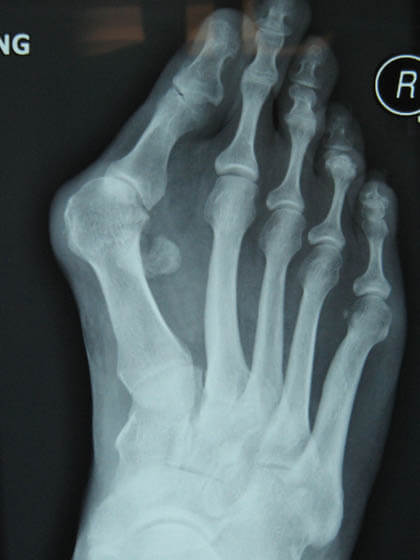

Toe Deformity Images